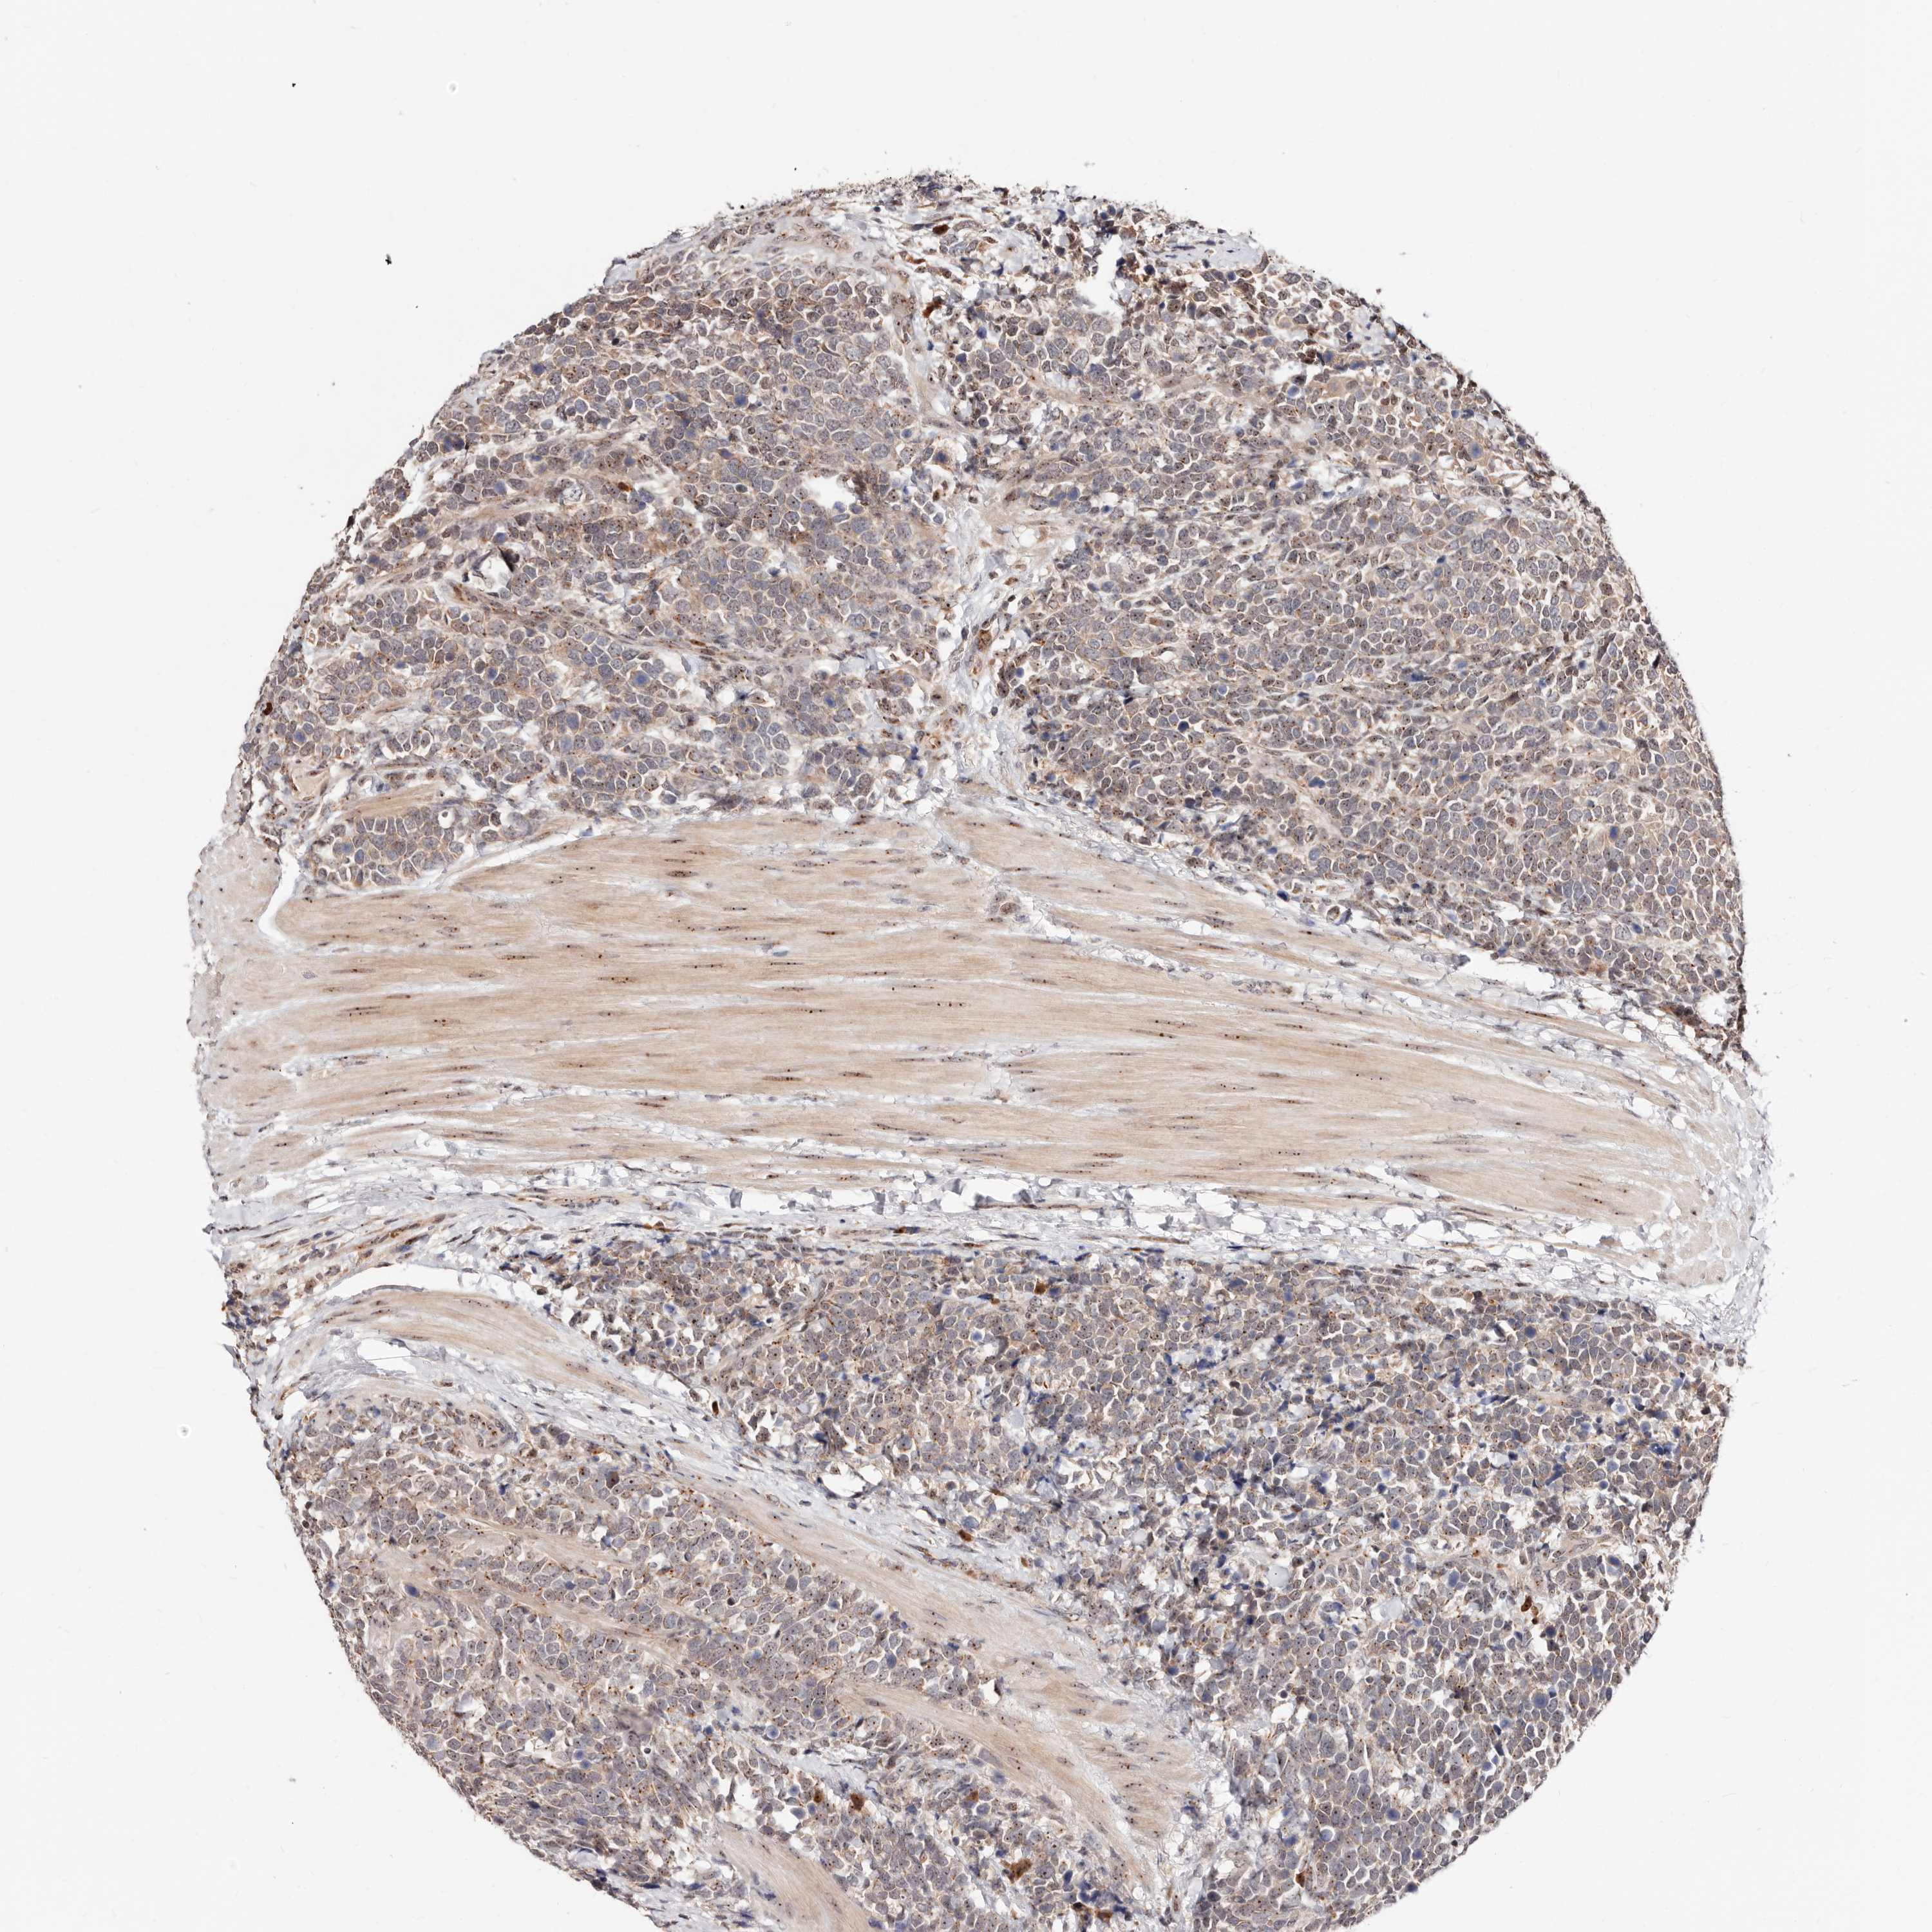

UROTHELIAL CANCER - Protein expressioni

A mouse-over function shows sample information and annotation data. Click on an image to view it in a full screen mode. Samples can be filtered based on level of antibody staining by selecting one or several of the following categories: high, medium, low and not detected. The assay and annotation is described here.

Note that samples used for immunohistochemistry by the Human Protein Atlas do not correspond to samples in the TCGA dataset.

Antibody stainingi

Antibody staining in the annotated cell types in the current human tissue is reported as not detected, low, medium, or high, based on conventional immunohistochemistry profiling in selected tissues. This score is based on the combination of the staining intensity and fraction of stained cells.

Each image is clickable and will lead to virtual microscopy that enables deeper exploration of all samples and also displays staining intensity scores, fraction scores and subcellular localization as well as patient and tissue information for each sample.

Antibody HPA029165

Antibody HPA029167

Antibody CAB028574

Staining

High

Medium

Low

Not detected

Intensity

Strong

Moderate

Weak

Negative

Quantity

>75%

75%-25%

<25%

None

Location

Nuclear

Cytoplasmic/membranous

Cytoplasmic/membranous,nuclear

Urothelial carcinoma, Low grade

Urothelial carcinoma, High grade